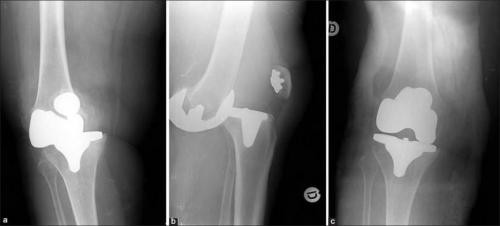

Реабилитация после эндопротезирования имеет первостепенное значение для обеспечения безболезненного функционирования сустава и улучшения качества жизни пациента. Операция попоказана для лечения болезненных и инвалидизирующих патологий, вызванных различными формами, тяжелыми травмами. Хирургом-ортопедом выполняется полная или частичная замена износившегося суставного соединения на его анатомически точную копию.

Искусственный имплантат состоит из металлических и пластиковых элементов, абсолютно безопасных для организма. Чтобы заново научить прооперированную конечность двигаться правильно, расширить диапазон доступных движений, требуются массажи, посещение физиотерапевтического кабинета, выполнение.